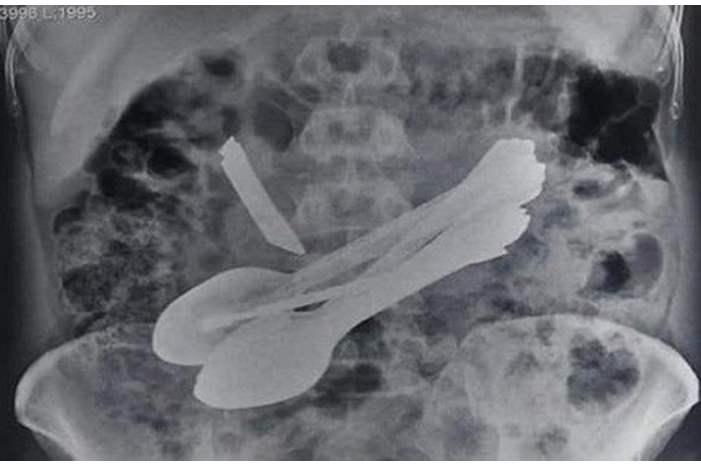

الوكيل الاخباري – واحدة من أغرب عملية جراحية على الإطلاق ، استخرج جراحون بالهند ملاعق وسكين وأشياء اخرى من معدة رجل مصاب بإضطرابات عقلية شديدة .

وتم نقل الرجل إلى المستشفى ليخضع إلى التصوير الإشعاعي ، إذ تم اكتشاف تلك الأدوات .

وظل الجراحون يعملون 4 ساعات لإستخراج 8 ملاعق، سكين مطبخ، فرشاتي أسنان، اثنين من مفكات البراغي وقفل باب من بطن الرجل .